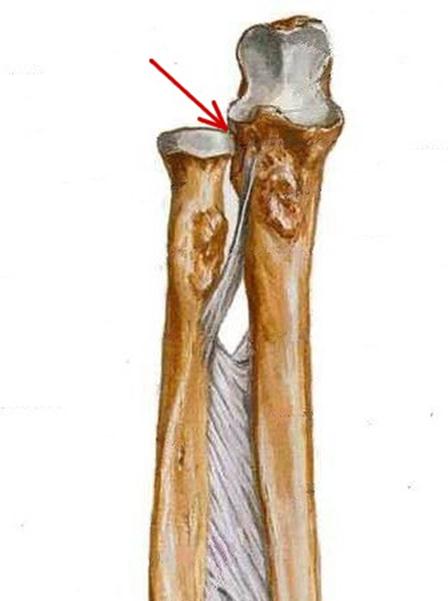

S: Стрелкауказывает на...

+:caput radii